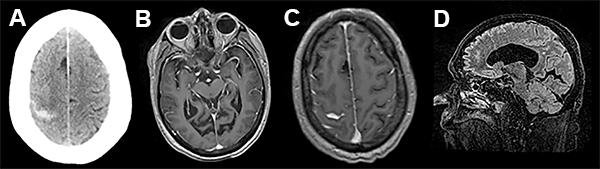

A las 72 hs de la segunda intervención comienza con cefaleas intensas, náuseas, trastorno del sensorio por lo cual se realiza nueva internación, evidenciando mediante TAC sangrado subaracnoideo (fig. 2).

Figura 2

En el presente trabajo, los autores reportan un evento hemorrágico cerebral como complicación de una fistula de líquido cefalorraquídeo (LCR) asociada a una cirugía espinal lumbar mini invasiva. Dicho evento se desencadenó 72 hs luego de la reparación de la fístula de LCR, presentándose como una hemorragia subaracnoidea de la convexidad cerebral. Esta complicación ha sido descrita por numerosos grupos,1-5 siendo la localización mas frecuente el cerebelo. Si bien las imágenes de tomografía y resonancia magnética nuclear evidencian la presencia de hemorragia subaracnoidea en el surco central derecho, llama la atención la asimetría de surcos con hipodensidad en el área premotora derecha, similar a los hallazgos asociados con una trombosis venosa. Más aún, considerando que el paciente tiene antecedentes de trombosis venosa profunda e ingresa a las 72 horas por trastornos del sensorio (difícilmente explicables sólo por una hemorragia subaracnoidea de la convexidad), no podemos descartar con las imágenes brindadas la presencia de trombosis venosa, complicación también descripta como consecuencia de una perdida de LCR.6-9 Si bien ambas complicaciones son de muy baja ocurrencia, es importante reconocer su existencia a la hora de evaluar un postoperatorio de cirugía espinal complicado con fistula de LCR en pacientes añosos.